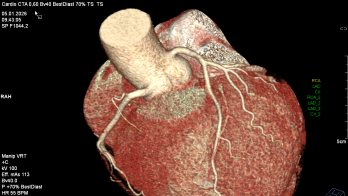

Jahrelang galt die Herzkatheteruntersuchung als das Nonplusultra zur Beurteilung der Herzkranzgefäße. Bezogen auf die Einwohner eines Landes ist Deutschland diesbezüglich Weltmeister. Und dennoch: Im Vergleich mit anderen westeuropäischen Ländern landet Deutschland bei der durchschnittlichen Lebenserwartung weit hinten. Der Grund: Im Kampf gegen Herz-Kreislauf-Erkrankungen, der häufigsten Todesursache, ist Deutschland deutlich weniger erfolgreich als andere Länder.

Es stellt sich also die Frage: Bekommen unsere Patienten die passende Diagnostik? Denn mittels geeigneter Diagnostik kann man die richtige Behandlung veranlassen. Viele Fragen lassen sich heute nicht-invasiv mittels kardialer Bildgebung (Kardio-CT & Kardio-MRT) beantworten und so eine individualisierte Therapie für unsere Patienten ableiten.

In Zusammenarbeit mit der Abteilung für Radiologie bieten wir ihnen das komplette Spektrum moderner kardialer Schnittbildgebung. Vereinbaren Sie einen Termin mit unseren Experten.